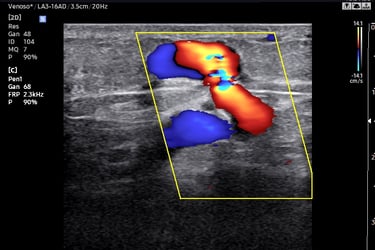

Ultrassom: ondas sonoras criam imagens das veias.

Doppler: identifica a direção e velocidade do sangue (cores no aparelho indicam fluxo normal ou alterado).

O Doppler emite sons e mostra cores no monitor (fluxo sanguíneo).

O Que o Doppler Revela Sobre Suas Varizes?

Mapa Venoso: localização exata das veias doentes.

Grau de Refluxo: se há sangue retornando (principal causa de varizes).

Coágulos (trombose): risco de complicações graves.

Função Valvar: se as válvulas das veias estão funcionando.